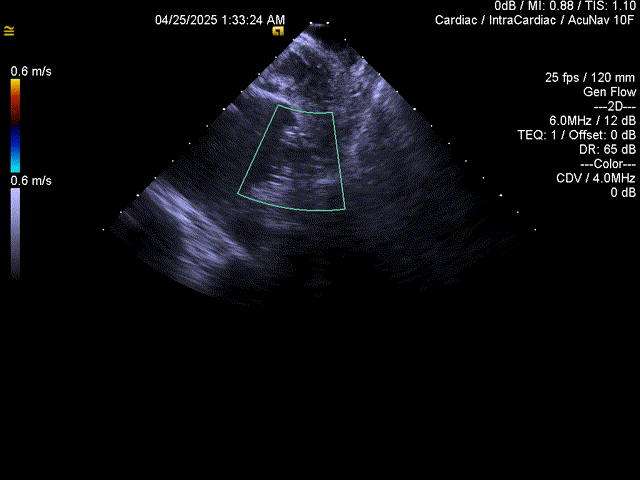

置入心腔内超声,成功房间隔穿刺

ICE引导房间隔穿刺

ICE下穿房间隔

ICE下评估PASS原则

封堵器位置及压缩比良好,多普勒检查无残余分流